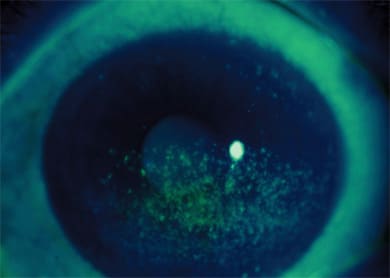

"If you look at the aqueous-deficient category, the presence or absence of Sjogren syndrome is often helpful in making therapeutic decisions, just because you know the likelihood of the severity of the disease," says Dr. Foulks. For evaporative dry eye, on the other hand, the most common cause is meibomian gland dysfunction, or lid margin disease (Figure 1). "That's an important feature to recognize because it has management implications," he says.

Figure 1. Meibomian inspissation — one form of meibomian gland dysfunction.